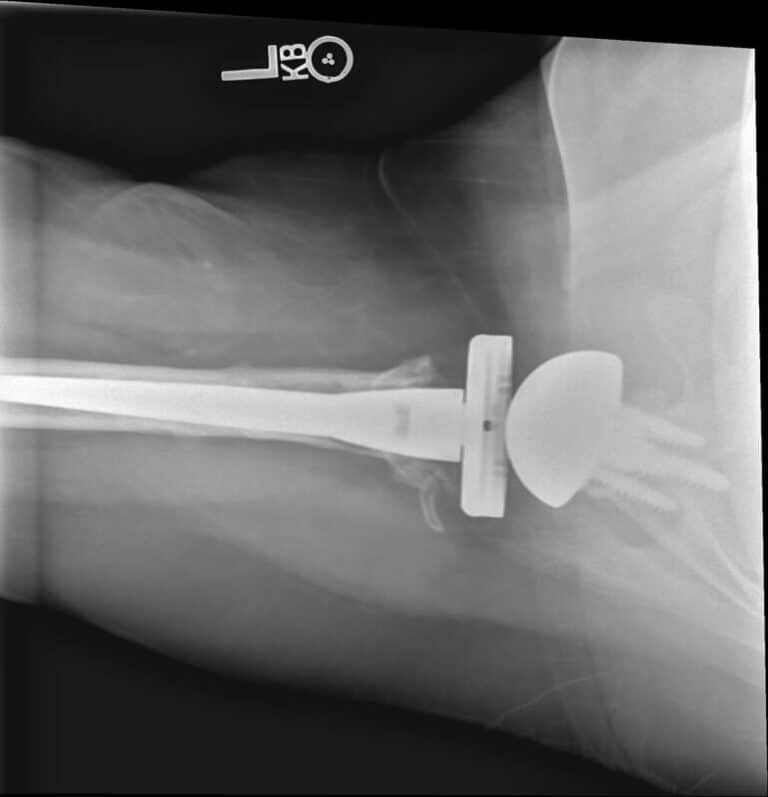

American Shoulder and Elbow Surgeons > Stryker/Wright/Tornier, Revive

Stryker/Wright/Tornier, Revive